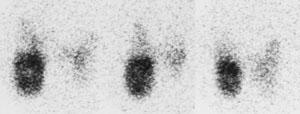

The most common site for distant metastatic disease is the lung [22]. Overall, men have a higher incidence of pulmonary mets. Between 50-60% of metastatic pulmonary lesions will concentrate radioiodine [6]. Patients with iodine concentrating pulmonary metastases have a 5-year survival rate of 60% compared to 30% for tumors which do not concentrate radioiodine [13]. The early (pre-radiographic) scintigraphic diagnosis and I-131 therapy of lung mets appears to be the most important element in obtaining both a significant improvement in survival rate and a prolonged disease free time interval in these patients. In patients with a negative CXR, but positive I-131 scans, there was a 10 year survival rate of 96% and a complete disease remission rate of 80% following I-131 therapy. In patients with both a positive CXR and a positive I-131 scan, the 10 year survival rate was significantly lower (40%) and complete remission was rarely achieved (4%). Patients with a positive CXR, but a negative I-131 scan had the worst prognosis with a 10 year survival rate of only 10% and no complete remissions. In summary- the presence of iodine concentrating pulmonary mets with a negative CXR appears not to influence mortality, however, non-concentrating micro- or macronodular mets do increase mortality risk.

Pulmonary metastases may appear on CT as micronodules (less than 5 mm), macronodules, or the lesions may be radiographically occult and only identified following I-131 imaging or treatment [22]. The micronodular pattern (miliary) of lung mets is invariably related to good I-131 uptake and a better prognosis, while macronodular (over 0.5 cm) mets frequently showed poor uptake and had an associated worse prognosis (fatal outcome was almost always observed in patients with macronodular mets and no I-131 accumulation). Reported 5 year survival rates are 100% for CT occult disease, 88% for micronodules, and 25% for macronodules [22].

Diffuse lung metastases: The patient was an 8 year old female with thyroid cancer. The I-131 exam demonstrated diffuse pulmonary tracer accumulation consistent with metastatic disease. The CXR demonstrated multiple small pulmonary nodules (Click CXR to enlarge image) |